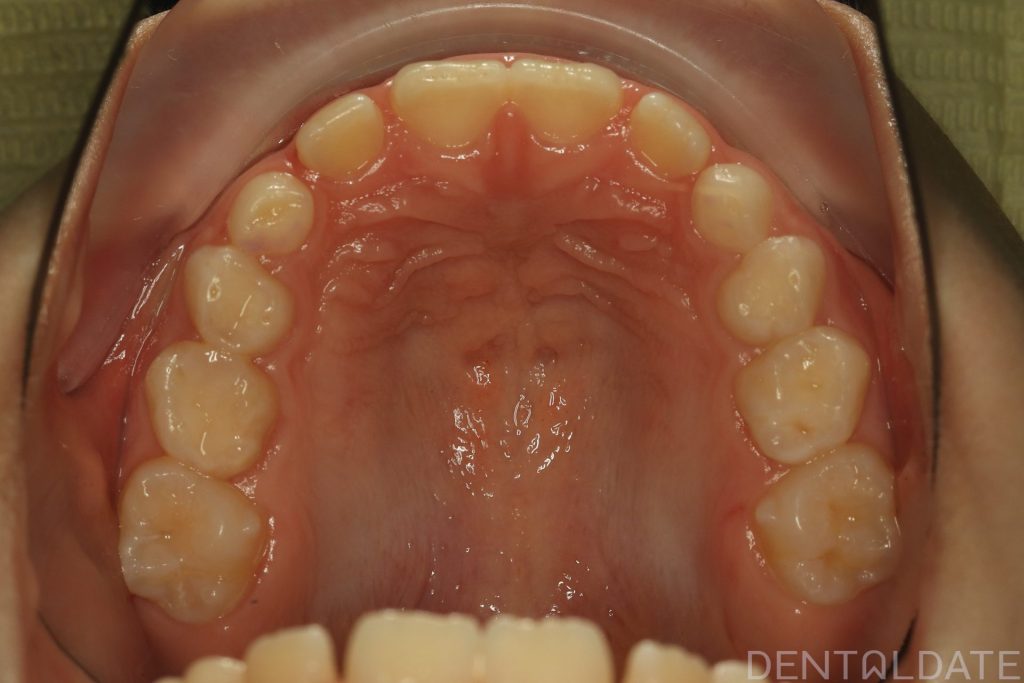

Parents sought an orthodontic consultation due to concerns about the aesthetics of their child’s smile.

To achieve harmony between function and aesthetics, a Haas appliance was used, followed by a myofunctional appliance.